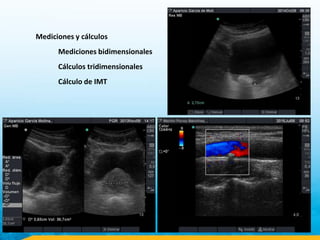

Mediciones y cálculos

Mediciones bidimensionales

Cálculos tridimensionales

Cálculo de IMT